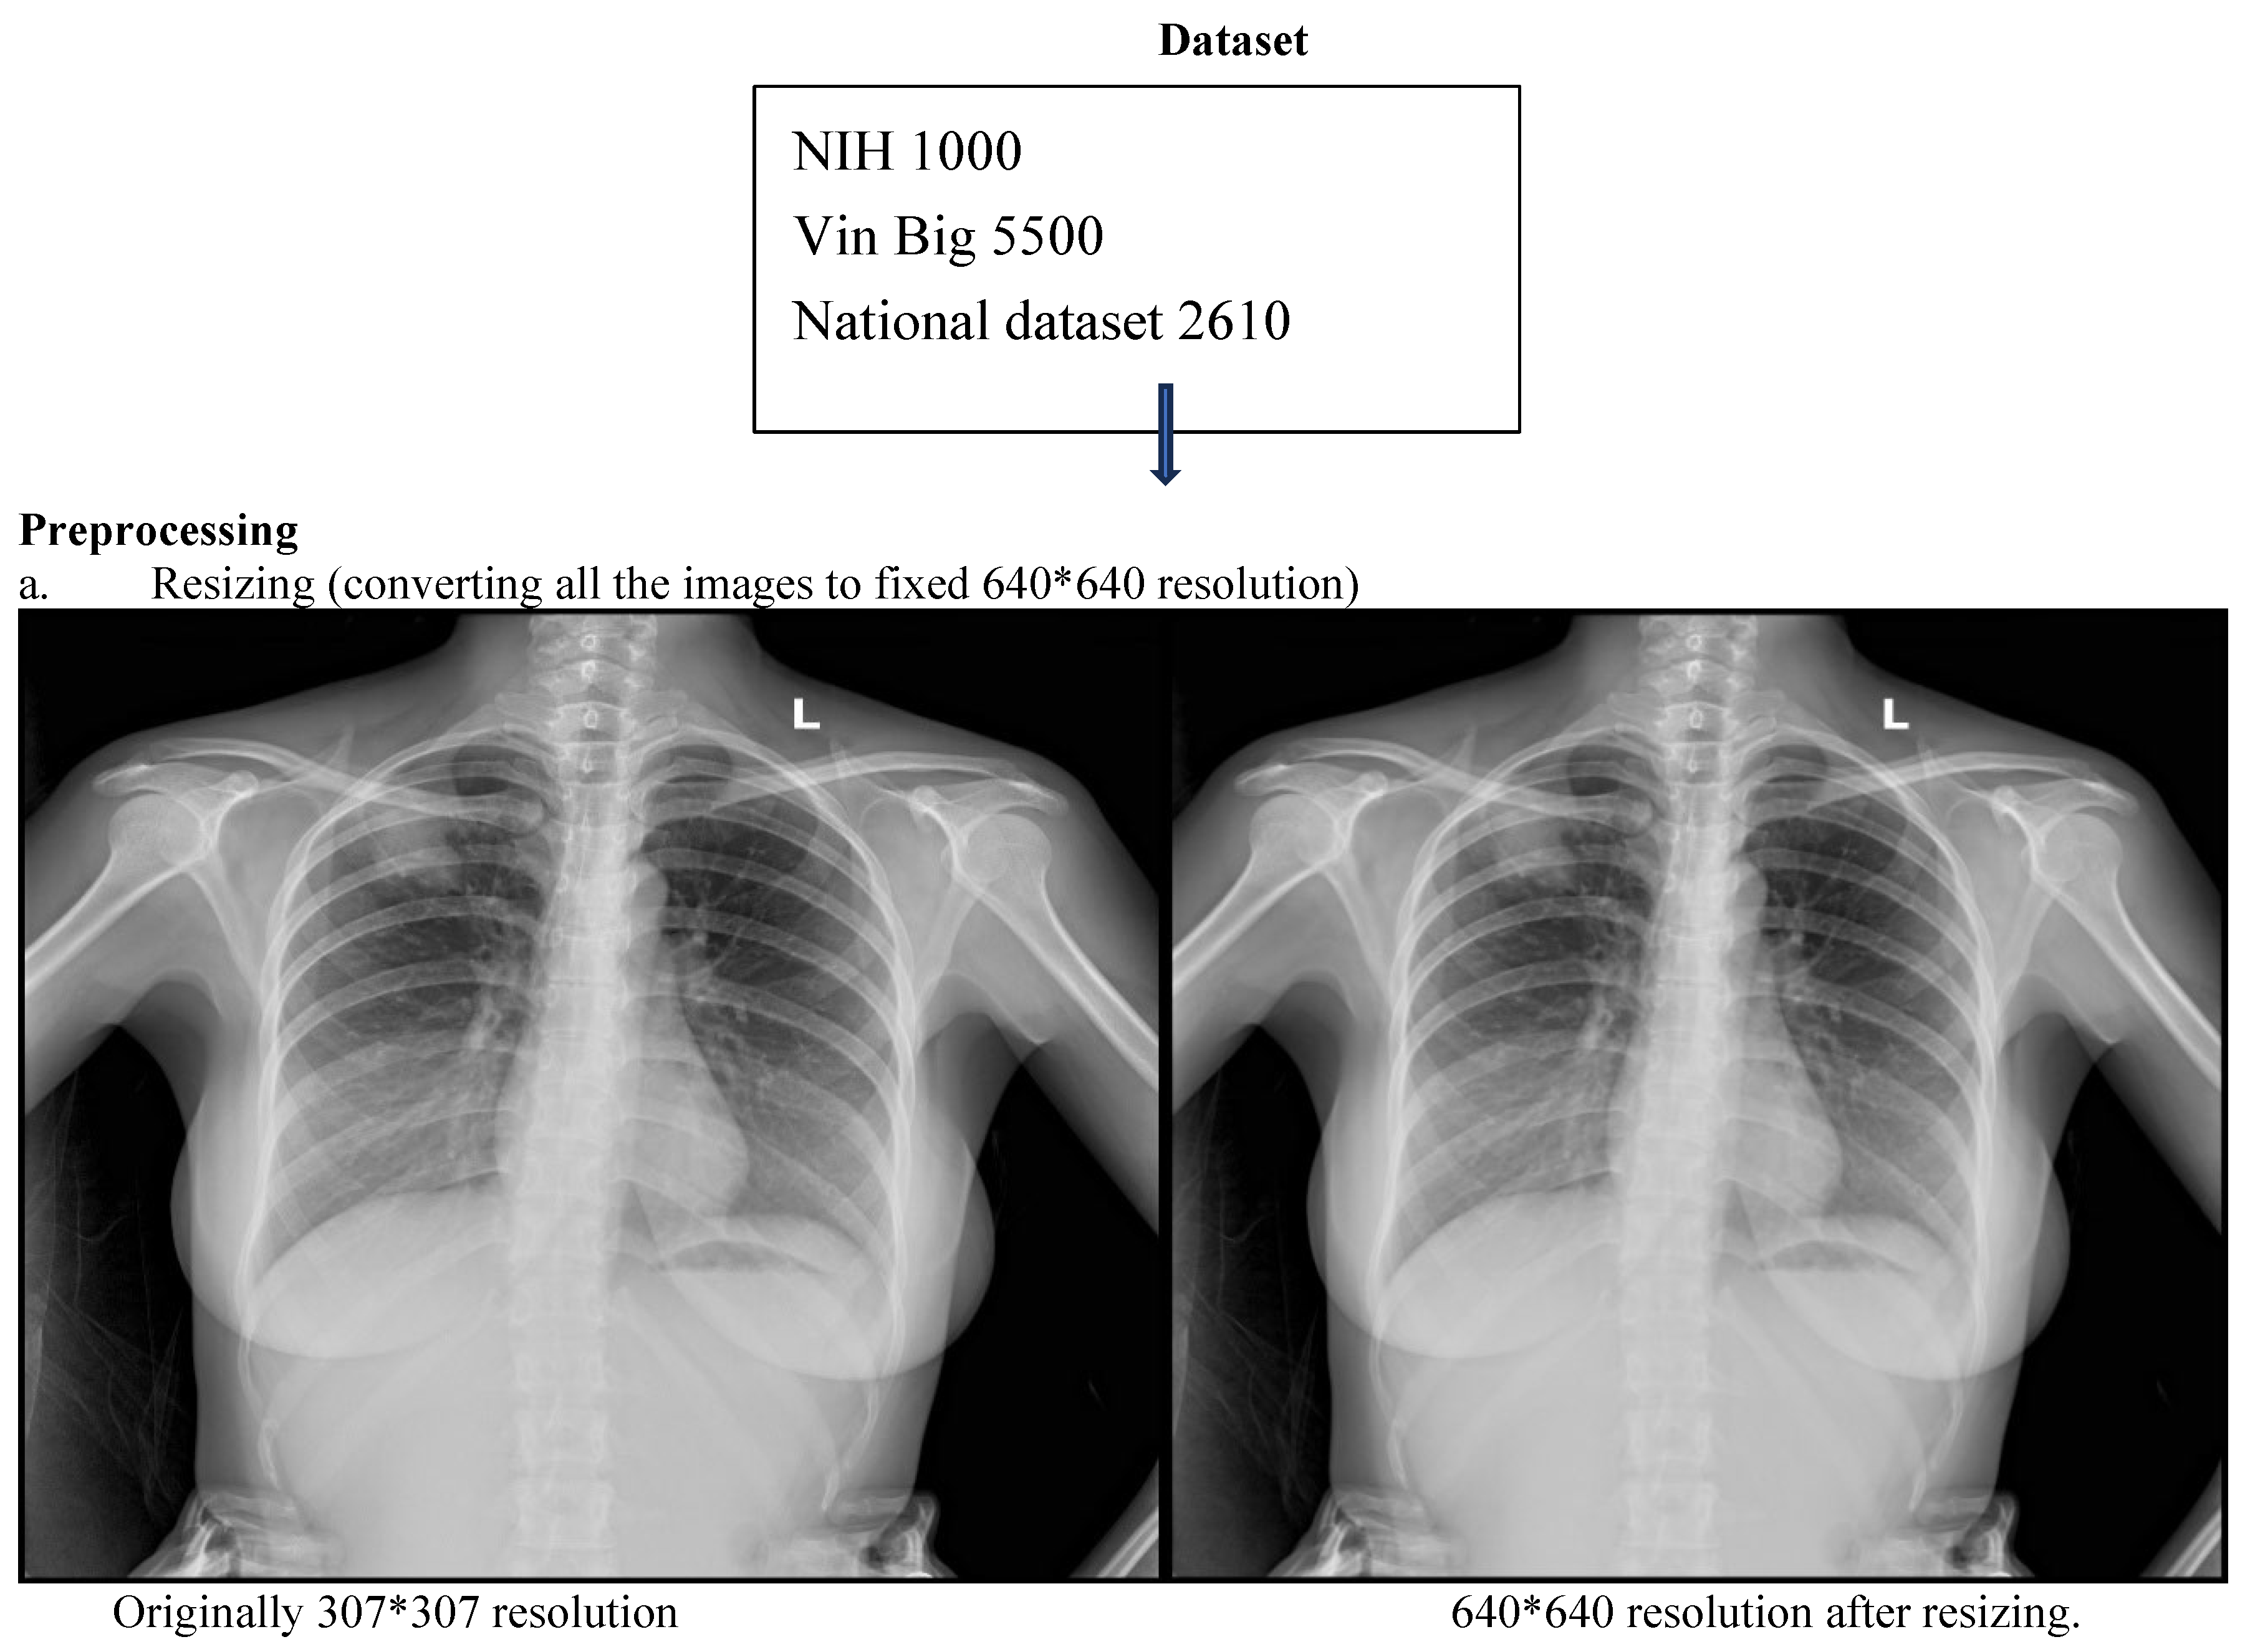

This retrospective study developed and evaluated a deep learning system for automated detection and localization of thoracic abnormalities on chest radiographs. The model was pretrained on two public datasets: the Vin Big Chest X-ray dataset (5500 images) and the NIH ChestX-ray dataset (1000 images). Domain-specific fine-tuning was conducted using adult chest radiographs acquired from the Emergency Department, Intensive Care Unit, and Outpatient Clinics of Tribhuvan University Teaching Hospital (TUTH), Nepal, between 1 January 2024 and 1 January 2025.

3.2. Preprocessing and Augmentation

All radiographs were resized to 640 × 640 pixels and normalized using a two-step strategy: (i) Min–max normalization to scale pixel intensities to [0, 1]. (ii) Z-score normalization using dataset-level mean and standard deviation.

Figure 1. CNN workflow pipeline depicting data sources, preprocessing and bounding box outputs.